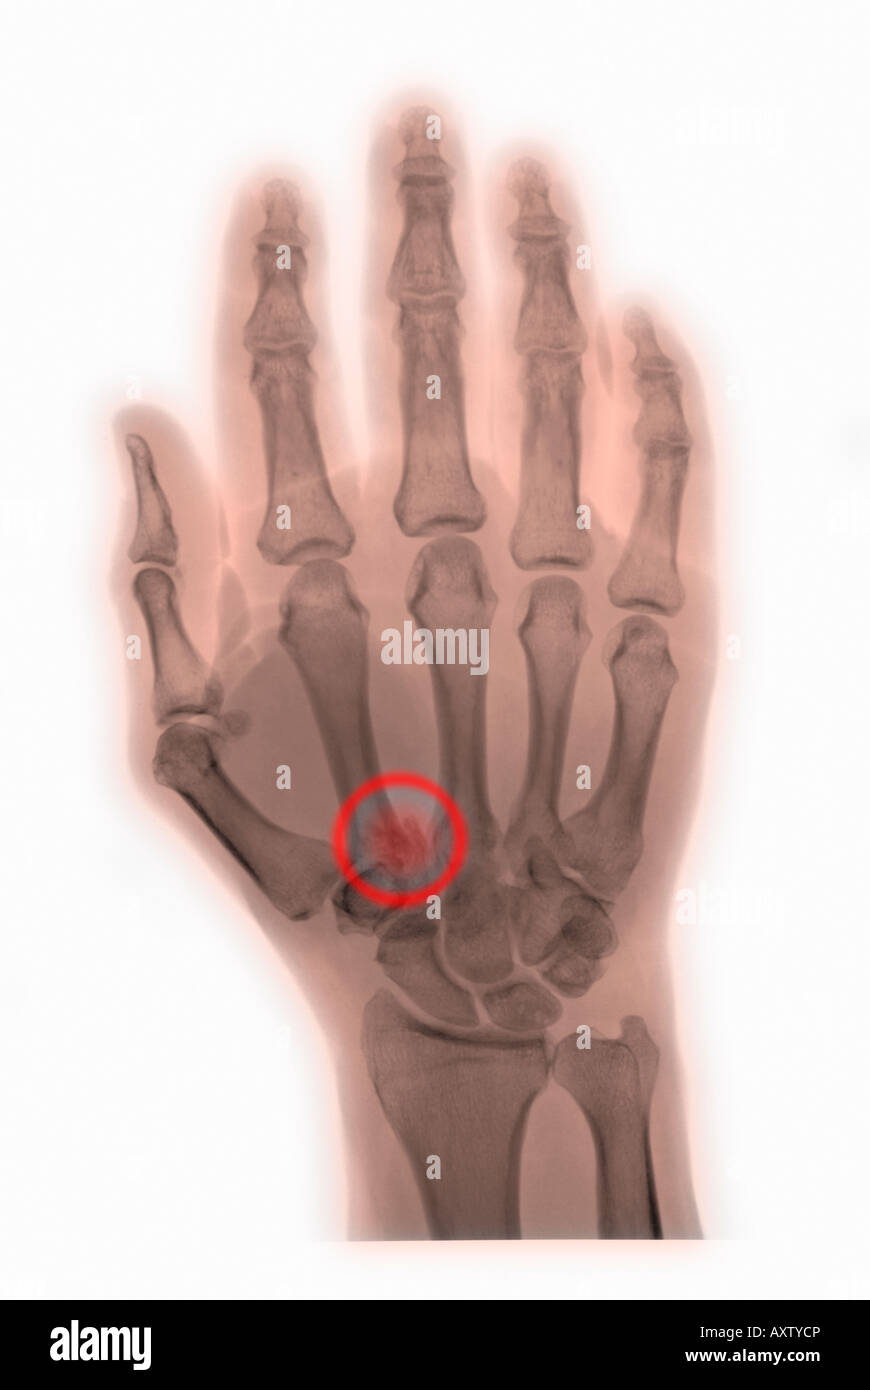

From www.alamy.com

xray of the hand of a man with a fracture of the first metacarpal Fracture From Punching Boxer’s fractures get their name from one of the most common causes, which is punching something. Boxer’s fractures get their name for how they usually happen — punching something. A boxer’s fracture is a fracture (broken bone) of the hand. A boxer’s fracture is a broken bone in your hand. More specifically, it is a fracture of the neck of. Fracture From Punching.